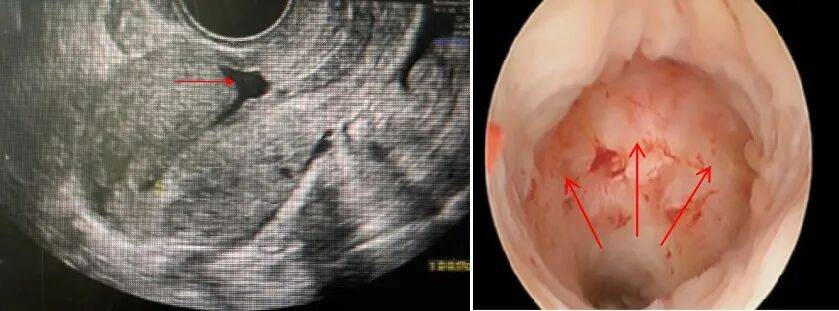

超声检查

初步筛查的“首选”。该检查方便、无创,能清晰显示子宫切口处的凹陷,还可测量憩室的大小、深度及残余肌层厚度。尤其在经期或异常出血时检查,能更清晰地观察到憩室内的经血,准确率更高。

宫腔镜检查

诊断金标准,兼具检查与治疗功能

宫腔镜通过细小镜头直接进入宫腔,能清晰观察到憩室的位置、大小,甚至憩室内的内膜情况。对于无生育要求、轻中度症状的女性,可在诊断的同时进行憩室开渠治疗,一举两得,但对于有生育需求或症状显著的女性不推荐,因为憩室开渠手术存在破坏宫颈结构且无法加强残余肌层厚度甚至让肌层更薄的缺点。